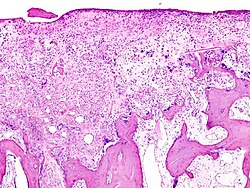

Patološka anatomija

Artroza je bolest koštano-mišićno-zglobnog sustava nastala uslijed trošenja hrskavice zbog prirodnog starenja, prethodnih oštećenja zglobova, te brojnih drugih etioloških faktora. Artroza predstavlja kroničnu degenerativnu promjenu jednog ili više zglobova, okarakteriziranu oštećenjem hrskavice koja prekriva zglobne površine i sekundarnim promjenama kosti koja leži ispod nje. Za razliku od drugih oblika artritisa (postoji oko 100 različitih vrsta), artroza nema utjecaja na unutarnje organe.

Kod artroze se hrskavica troši, povećavajući tako uzajamno trenje kostiju koje tvore zglob. To uzrokuje bol i oticanje, kao i gubitak pokretljivosti zgloba. Tijekom vremena, započinje prekomjerno izrastanje kosti duž zglobnog ruba kojeg nazivamo koštanim izraslinama ili osteofitima. Oni mogu pridonijeti gubitku pokreta u zglobu i povećanju osjećaja boli. Ove se izrasline mogu čak i slomiti i zaglaviti u zglobnom prostoru, što prouzrokuje još jače bolove i oštećenja.